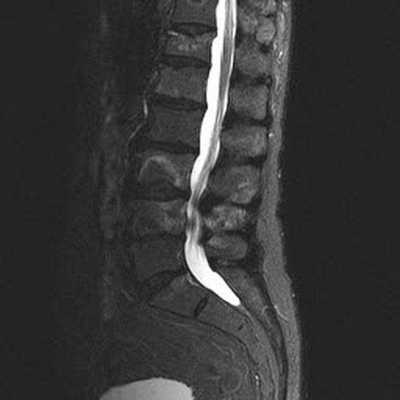

Стеноз позвоночного канала поясничного отдела на снимке МРТ

Для эффективного лечения болевого синдрома в области нижних отделов спины необходимо установить природу данного явления и уточнить локализацию патологического очага. Чаще в подобной ситуации лечащий врач рекомендует сделать МРТ пояснично-крестцового отдела, что показывает состояние морфологических элементов позвоночника и окружающих структур.

На снимках, полученных в результате магнитно-резонансной томографии, видны травматические повреждения спинного мозга при нарушении целостности тел позвонков, хрящей. Определяются разрывы и растяжения мышечной ткани, связочного аппарата. При компрессионных травмах МРТ визуализирует состояние церебральных структур, выявляет участки сдавливания нервных корешков.